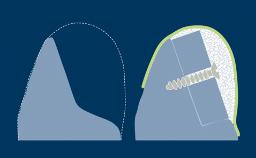

- select the appropriate type of provisional prosthesis

- specify which materials are needed to fabricate the prosthesis

- list the various techniques to fabricate the prosthesis